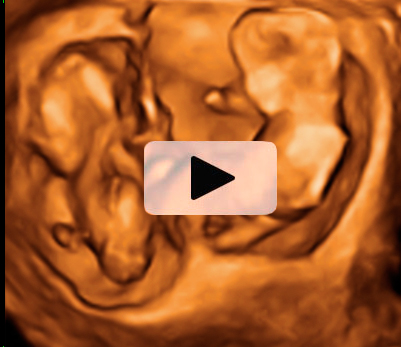

Ecografía Embarazo 4D Semana 12 - ANOMALÍAS CROMOSÓMICAS